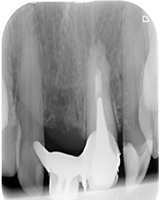

Pacjentka zgłosiła się z bólem. Ząb prawa dolna czwórka po leczeniu kanałowym. Nawracające dolegliwości bólowe, od kilku lat okresowo zaostrzające się. Podjęto decyzję o rewizji leczenia kanałowego. Udróżniono kanał korzeniowy, oraz odnaleziono kanał dodatkowy. Zdjęcie początkowe i zdjęcie po leczeniu endodontycznym pod mikroskopem.